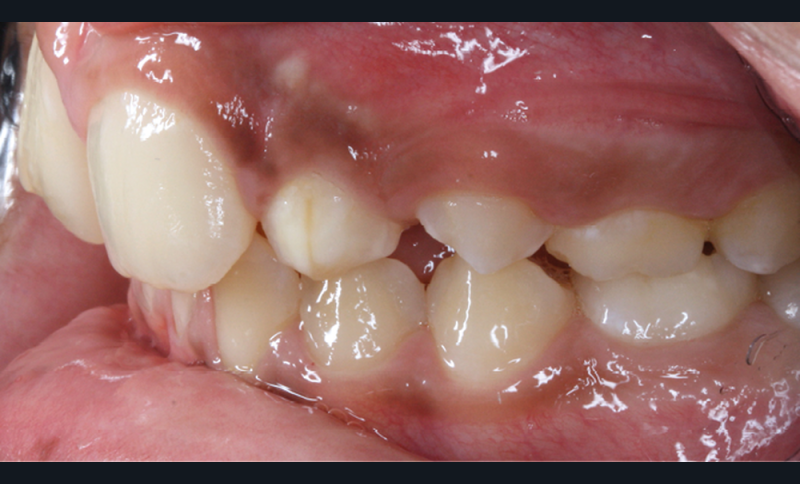

Antony, 11 ans se présente initialement pour une demande esthétique concernant ses deux incisives centrales qu’il trouve trop grosses (fig. 1a-c).

Le profil est convexe et associé à une inocclusion labiale au repos. Il s’agit d’une classe II squelettique sur un schéma facial normodivergent. Les rapports occlusaux sont de classe II bilatérale (complète au niveau molaire) avec des incisives inférieures vestibulo-versées. La 21 est géminée et la 11 vraisemblablement fusionnée avec un germe surnuméraire, sans altération de la formule dentaire. Du fait du diamètre mésiodistal fortement augmenté des incisives centrales, et du manque de place à l’arcade maxillaire qui en découle, les 12 et 22 sont en inversé d’occlusion en palato position. Les 53 et 63 sont persistantes sur l’arcade avec une inclusion en transposition incomplète de la 13, dont la cuspide se situe entre la racine de la 12 et celle de la 11 résorbée (fig. 1d-g).